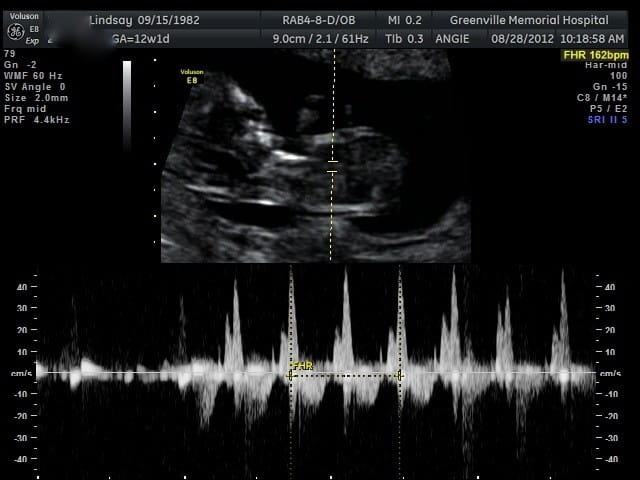

Thực tế chỉ vào khoảng tuần thứ 9 hoặc thứ 10 của thai kỳ là mẹ có thể nghe được tim thai của bé. Lúc này nhịp tim của thai nhi thường đập 170 nhịp, bác sỹ sẽ đặt một thiết bị siêu âm cầm tay (doppler) ở trên bụng của mẹ để giúp khuyếch đại âm thanh, nhờ vậy mà các mẹ có thể dễ dàng nghe được âm thanh nhịp tim thai của con.

Nhịp tim thai trung bình sẽ dao động từ 120-160 lần /phút.

Tim thai của trẻ cũng sẽ gia tăng về khối lượng và kích thước theo sự phát triển của cơ thể. Tim thai trung bình của bé sẽ dao động từ 120-160 lần/phút. Tuy nhiên nhịp tim có thể tăng nhanh đến 180 lần/phút nếu như em bé cựa quậy nhiều hoặc mẹ hồi hộp quá.

Nhịp tim thai cũng sẽ có sự thay đổi theo tuần tuổi sẽ khác nhau, tuỳ từng tình trạng của thai nhi mà nhịp tim khác nhau nhưng cũng đều dao động tầm 120-160 lần/phút.

Trường hợp nếu như nhịp tim của thai nhi mà đập nhanh hơn 180 lần/phút thì đây là dấu hiệu bất thường, có thể báo động về sức khỏe mẹ hoặc sức khoẻ thai nhi.